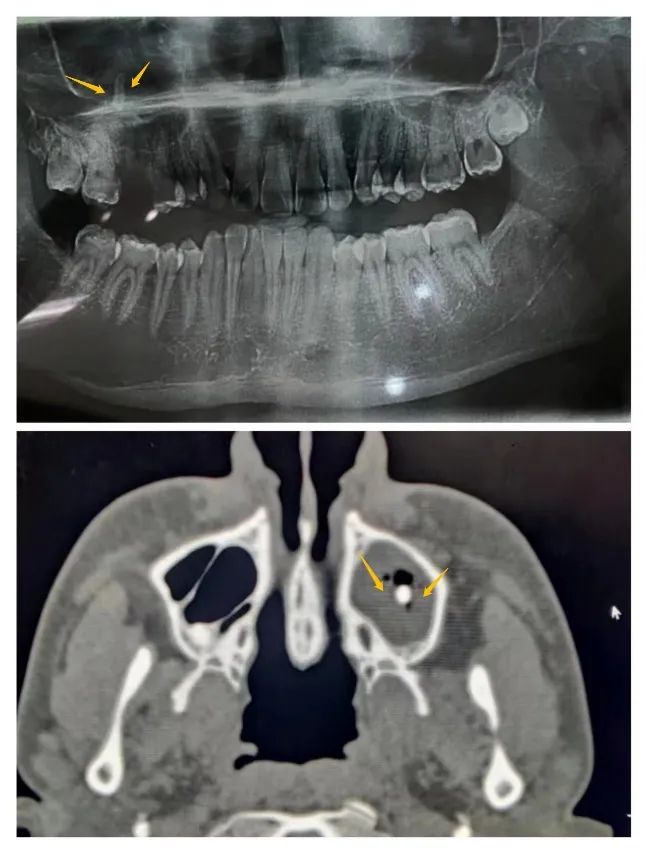

影像资料显示牙根位于上颌窦内

第二天,患者早早来到五官科病房,薛徽主任进行系统的临床查体,检查发现右侧上颌第一磨牙区颊侧牙槽窝空虚,腭侧牙根尚未拔除,捏鼻鼓气时可见大量气泡自拔牙窝涌出,考虑上颌窦-口腔已穿通,但牙根的具体位置尚不明确。紧接着,薛徽主任为患者开具上颌骨CT平扫检查单,进行冠扫及口腔全景片检查。影像学检查结果显示疑似牙根样高密度影位于上颌窦中央略偏右侧前壁位置,窦腔内可见大量低密度影包绕牙根,考虑为拔牙后血性分泌物或异物进入窦腔后机体产生的炎性分泌物,这给异物取出带来了极大的难度。